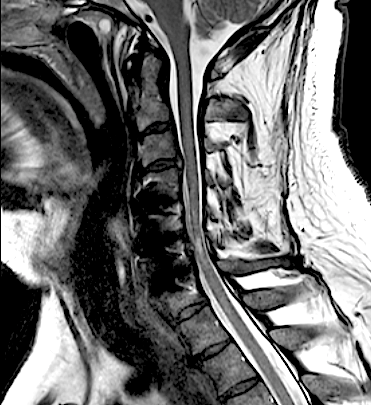

El paciente presentó a las 24horas un agravamiento de la paresia C7 derecha indolora, sin cambios en el puntaje (EMS) de su mielopatía, por lo que se decidió realizar una RM cervical urgente.

El resultado de la RM cervical planteaba dudas si era necesario o mandatorio realizar una descompresión posterior complementaria. Sin embargo, los parámetros clínicos no sugerían una compresión medular: la evolución lenta a la mejoría de su paresia, la ausencia de progresión de su mielopatía y la ausencia de dolor resultaron determinantes para que se adoptara una actitud conservadora. El paciente fue dado de alta (en plena pandemia de covid) y la evolución fue buena a pesar de que no pudo completar la rehabilitación. Se realizó nueva RM y RX cervical a los seis meses que resultó mucho más concluyente.

RM postoperatorio